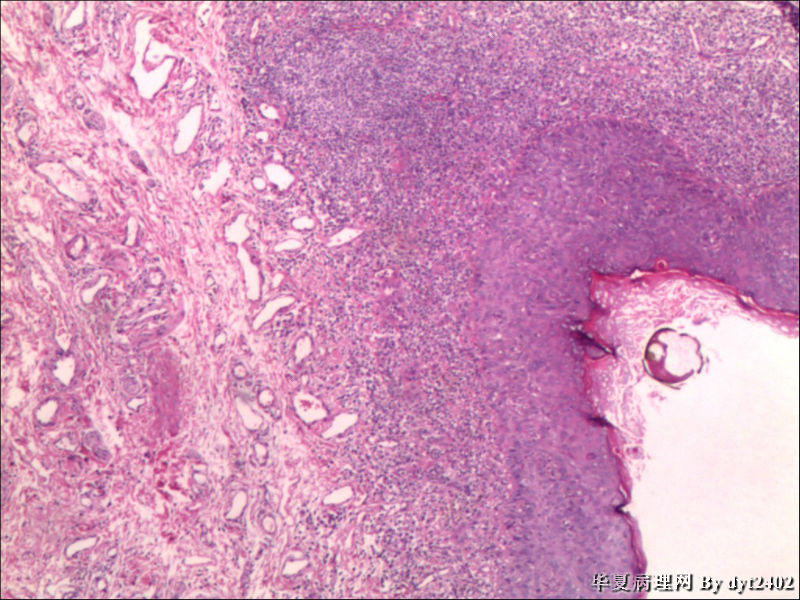

这样的外阴病变 发个原位癌是否合适?

• 这样的外阴病变 发个原位癌是否合适?图1

图1

VIN III,做个银染或者标个免疫组化看一下基底膜是否完整。

原位癌够了,不排除其他地方有浸润。

似乎有浸润了

VIN III

看上去好像还完整 只是经常看见图5 那样结构的就觉得可能还有更重病变